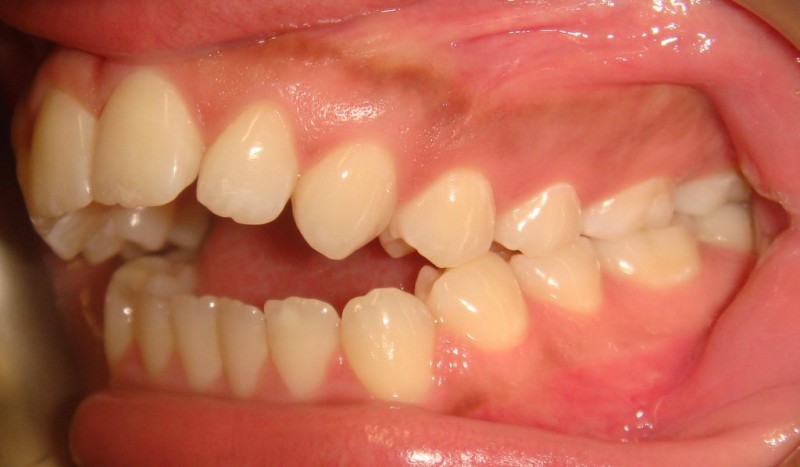

Pretreatment - Patient on Presentation